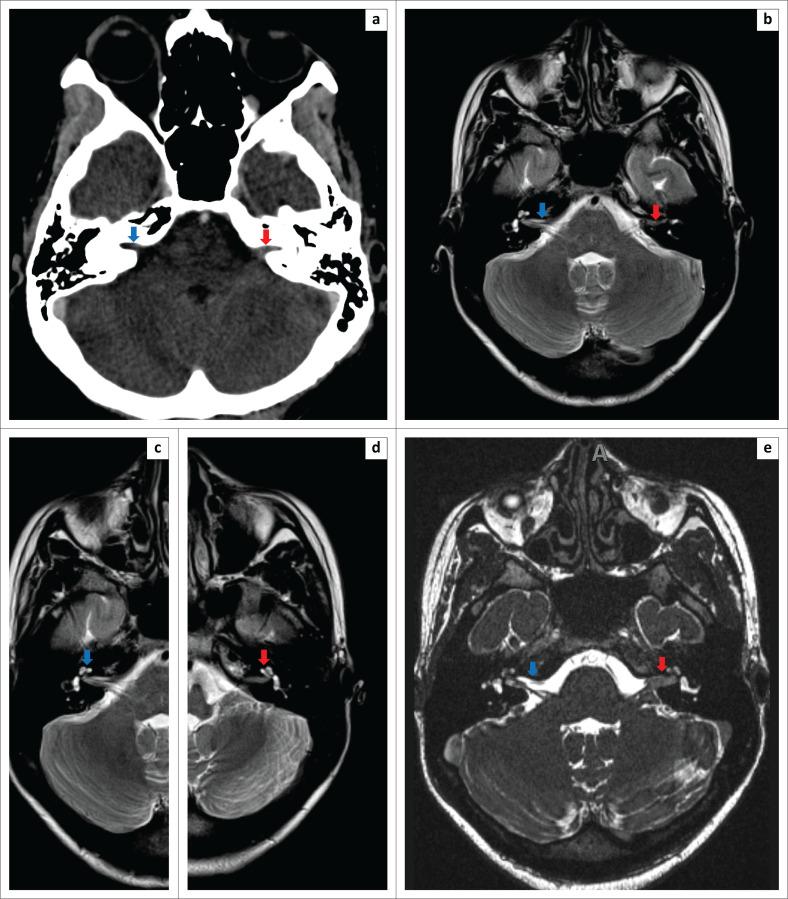

Bilateral acute hearing loss is rare, and the aetiology is poorly defined. Less common treatable pathologies such as otosyphilis must be part of the differential diagnosis and should be actively excluded. We present a case of a 23-year-old woman who developed acute bilateral hearing loss due to otosyphilis, confirmed on audiometry and laboratory tests. In this article, the CT, MRI and clinical findings are presented and discussed.

双侧急性听力损失较为罕见,其病因尚不明确。一些不太常见的可治疗病因,如耳梅毒,必须纳入鉴别诊断范围,且应积极排除。我们报告一例23岁女性因耳梅毒导致急性双侧听力损失的病例,听力测定和实验室检查确诊了该病。本文展示并讨论了该病例的CT、MRI及临床检查结果。